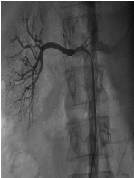

Acute Pulmonary Edema after Endovascular Treatment for Renal Artery Stenosis - Clinical Evolution after Angioplasty and Stenting in Moderate Stenosis:A Case Report

Thiago Andrade Macedo1*, Ligia Sayuri Teoi Coelho Borges1, Mateus Paiva Marques Feitosa1, Henrique Cotchi Simbo Muela2, Valeria Aparecida Costa-Hong1, Luiz Junia Kajita3, Luiz Aparecido Bortolotto1